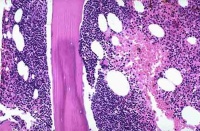

病理改变[编辑 | 编辑源代码]

恶性淋巴瘤在病理学上分成何杰金氏病和非何杰金氏病两大类,根据瘤细胞大小、形态和分布方式可进一步分成不同类型。

(一)何杰金氏病(HD) HD是一种特殊类型的恶性淋巴瘤,组织学诊断主要依靠在多形性炎症浸润背景上找到特征性R-S细胞。1965年,Rye国际会议确定分为四型:

1.淋巴细胞为主型(LP)HD2以中、小淋巴细胞增生为主,有时以组织细胞增生为主;典型R-S细胞不易找到。但常存在较多L-H细胞。

2.结节硬化型(NS)HD:以双折光宽胶原纤维束,将存在腔隙型R-S细胞的淋巴组织分隔成大小不一结节为特征,典型R-S细胞罕见。

3.混合细胞型(MC)HD:典型R-S细胞和H细胞多,炎性细胞明显多形性,伴血管增生纤维化

4.淋巴细胞消减型(LD)HD:除存在典型R-S细胞外,还可出现许多多形性R-S细胞(网状细胞型)或弥漫性非双折光纤维组织增生,反应性炎性细胞显著减少。